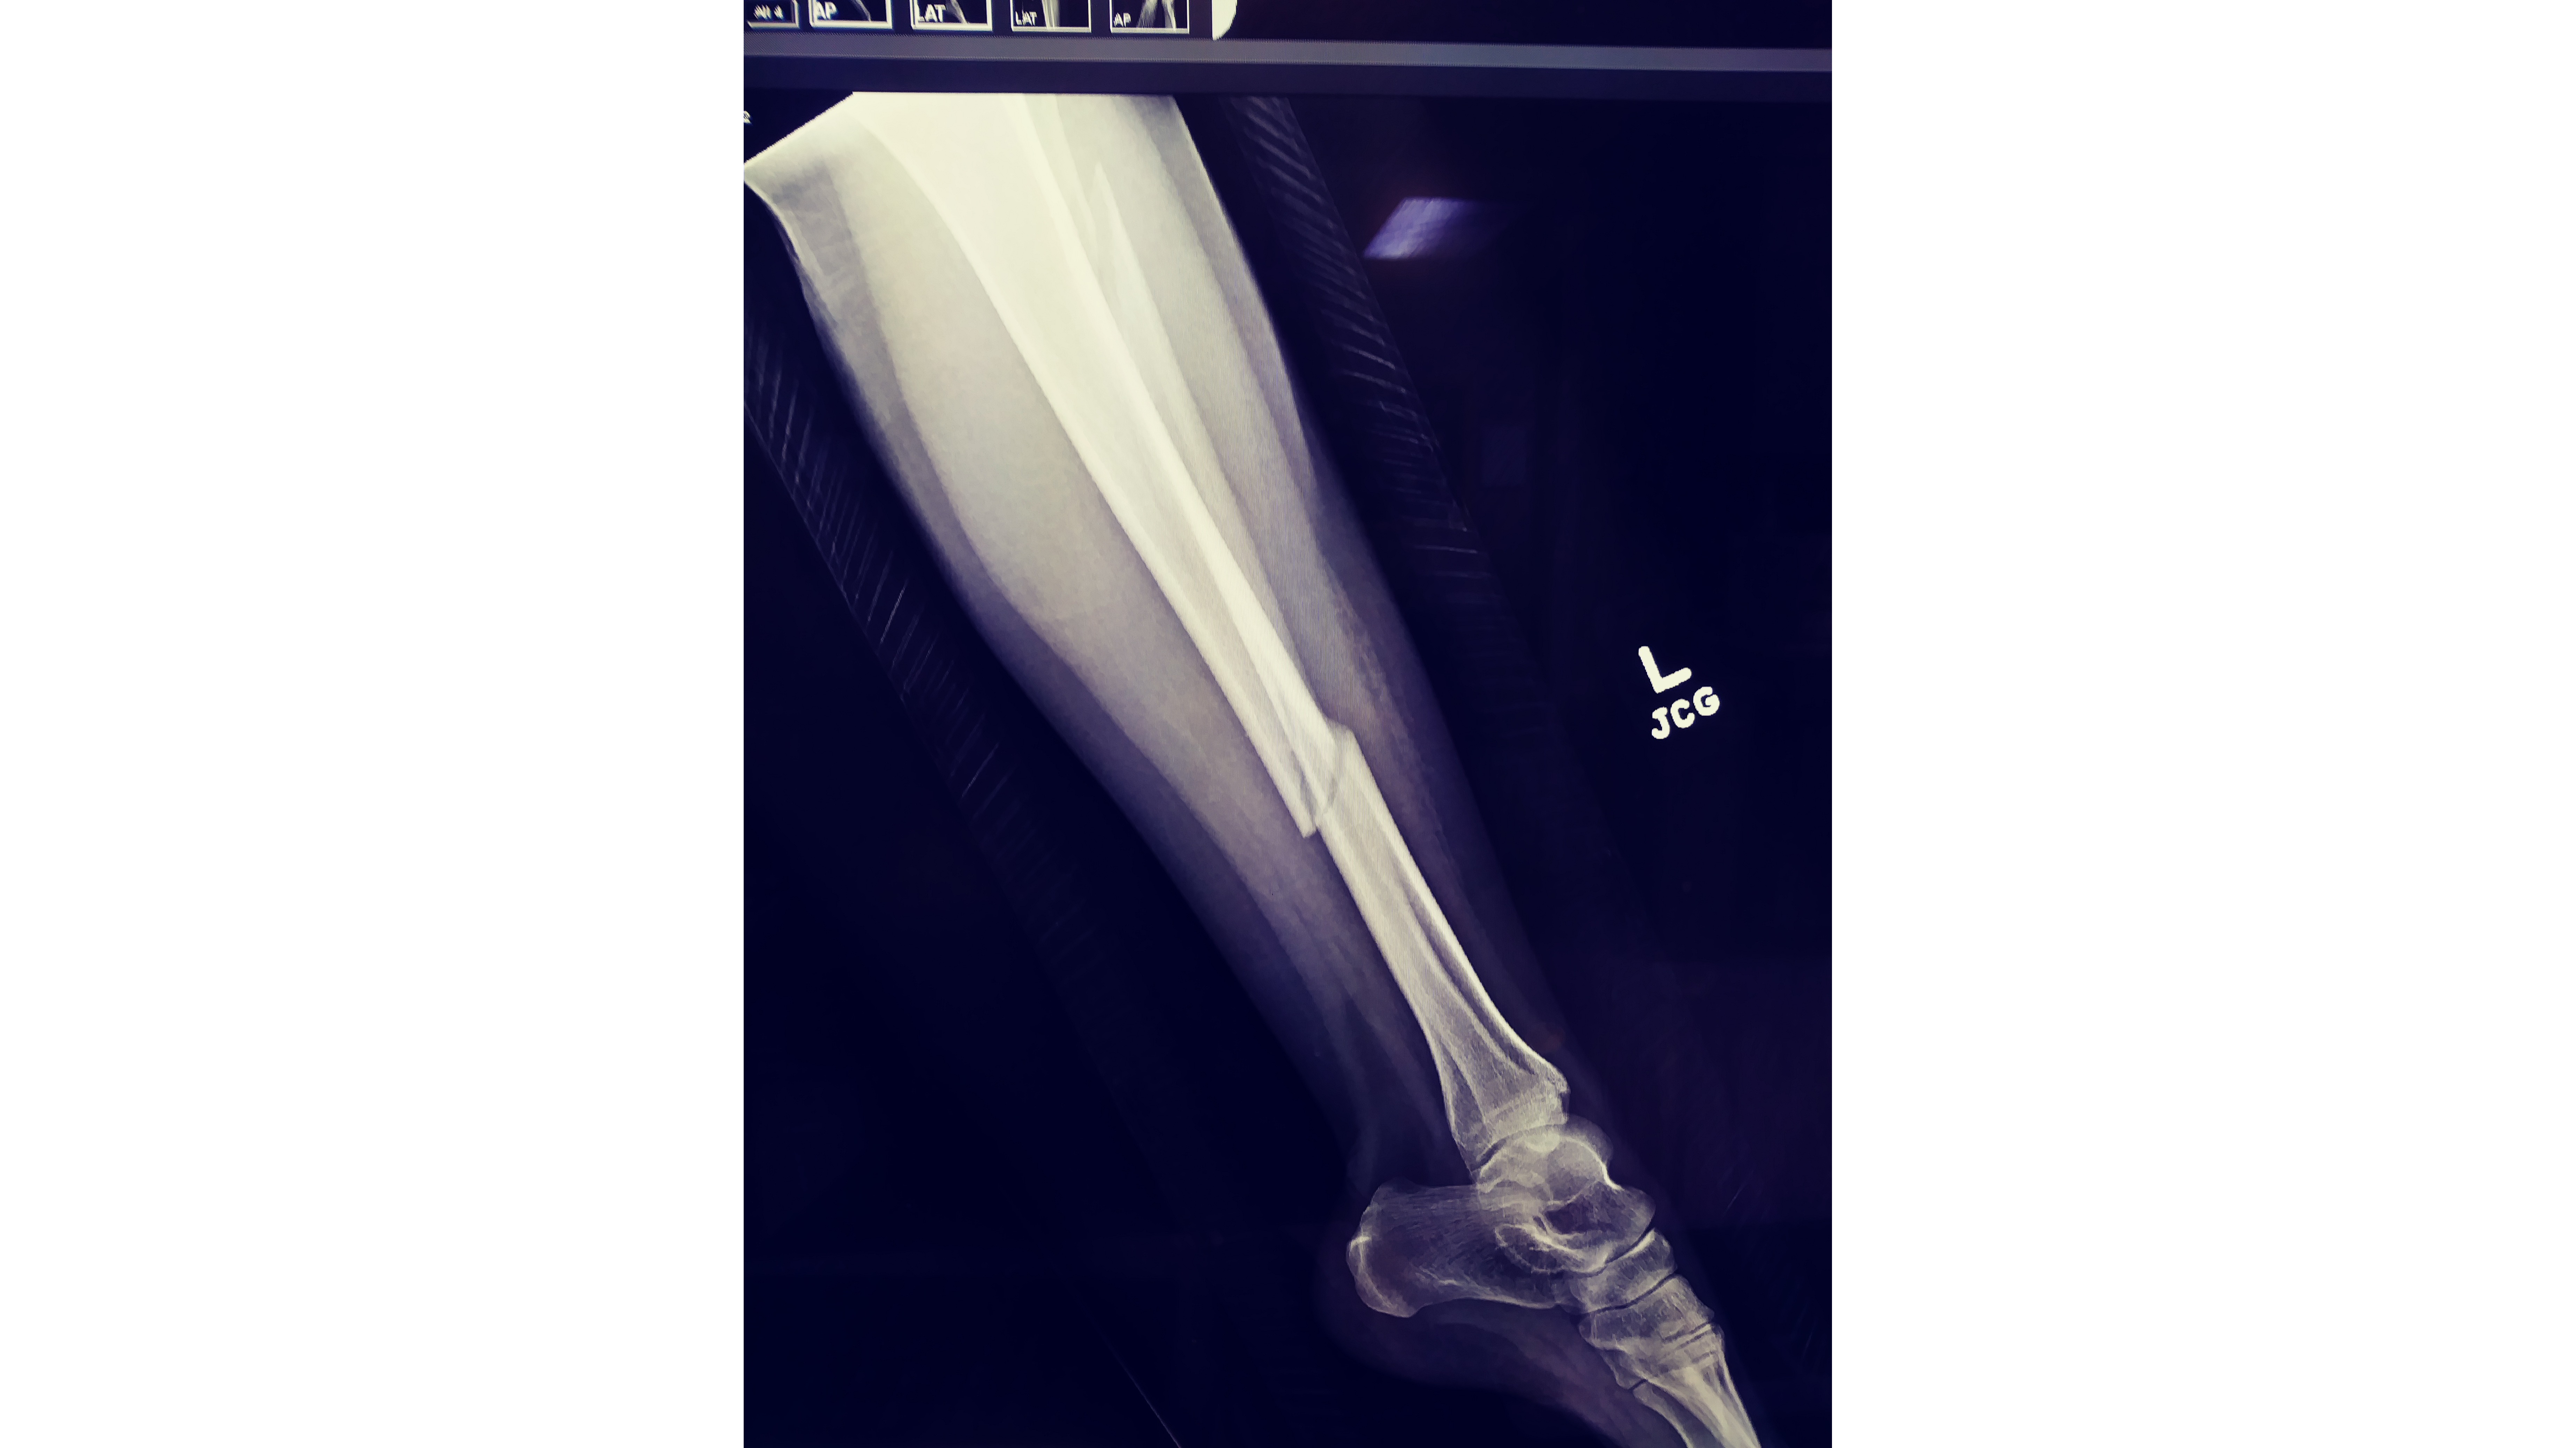

I had a bad fall which broke both bones in my left leg. 7 hr surgery. Lots of hardware and permanent nerve damage resulting in foot drop. My insurance does not cover the cost for this device.without it i can not flex my foot upwards to walk. I need a custom AFO built for my leg and foot so that i can try to get on with life and work again.